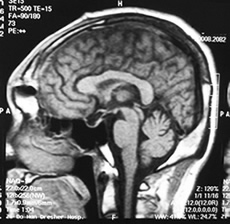

3.頭顱MRI 正常人垂體前葉MRI信號與腦灰質相似,神經垂體95%呈短T1高信號垂體上緣多呈下凹偏平,少數偶見平緩的微凸狀明顯的局部上凸者90%為垂體微腺瘤。正常垂體柄居中小於4mm,垂體柄移位是垂體病變的間接指征。MRI診斷垂體大腺瘤效果等於或優於頭顱CT能清楚的辨別垂體瘤與視神經視交叉的關係一般MRI診斷垂體微腺瘤不如頭顱CT,但近年用1.5T高場強MRI掃描對垂體微腺瘤診斷的敏感性提高到83%而頭顱CT僅為42%,以冠狀面和矢狀面影像最清楚。在T1加權像上呈局灶性低信號在T2加權像上呈局灶性高信號其特點表現:冠狀面垂體上緣局限性上凸,垂體腺高度增加,鞍底向下膨隆,雙側頸內動脈海綿竇段不對稱,病灶處向外下移位,強化後即刻掃描顯示微腺瘤呈局灶低信號,而正常垂體明顯強化。

MRI對顱咽管瘤的定性診斷不如CT,頭顱CT可顯示典型的鈣化灶,而MRI顯示鈣化效果欠佳,MRI的主要依據是:位於鞍上區是囊性腫物,增強後囊壁可呈環狀加強。